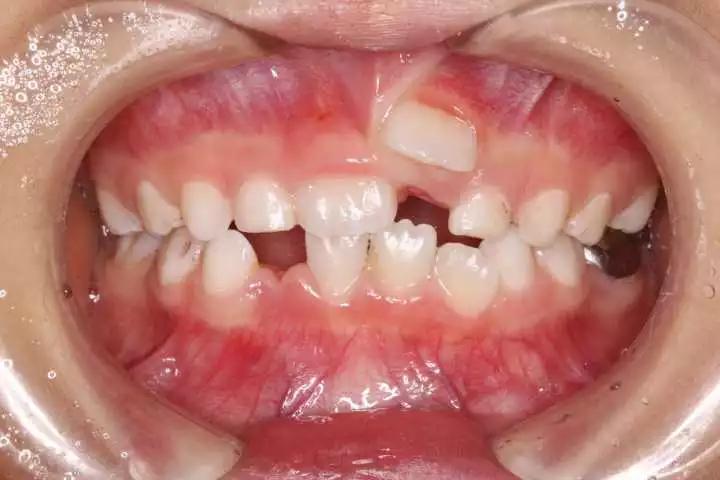

继承恒牙已萌出,乳牙未脱落(箭头指示继承恒牙)

长在外侧的双排牙